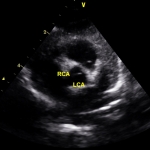

Υπερηχογράφημα (ECHO): φυσιολογική βασική ανατομία, φυσιολογικές διαστάσεις και λειτουργικότητα (συστολική και διαστολική λειτουργία, ελέγχθησαν και με ιστικό Doppler πέραν του συνήθους ελέγχου). Παρακάτω απεικονίζονται τα στεφανιαία. Ελέγχθηκε η έκφυση όχι μόνο με 2D, αλλά και με απεικόνιση της στεφανιαίας ροής με color Doppler (ασυνήθης πρακτική για παιδιά, θα εξηγηθεί ο λόγος στη συνέχεια).